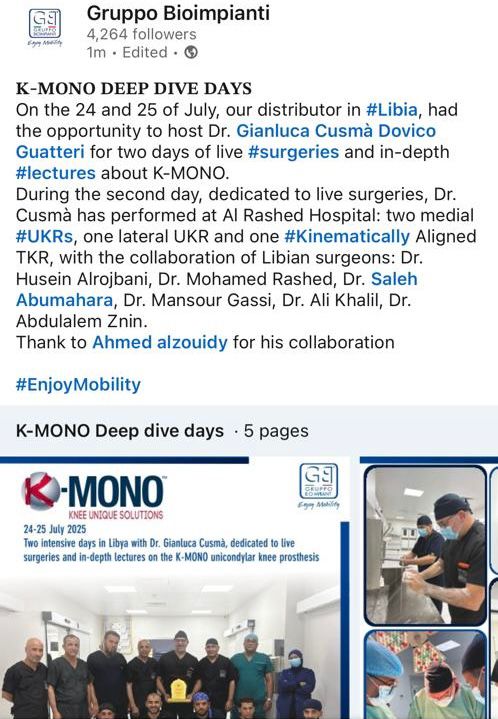

Keeping pace with the latest advancements in the health sector, and for the first time in Libya, three Partial Knee Replacement surgeries were successfully performed during the Fifth Knee Surgery Training Course, held in the city of Sabratha under the supervision of the Medical Specialties Board and the Libyan Society of Arthroscopy and Knee Surgery, at Al-Rasheed Hospital in Salah Al-Din.

This surgical procedure aims to replace only the damaged portion of the knee joint while preserving the healthy parts, and is used to treat unicompartmental knee osteoarthritis confined to a single compartment.